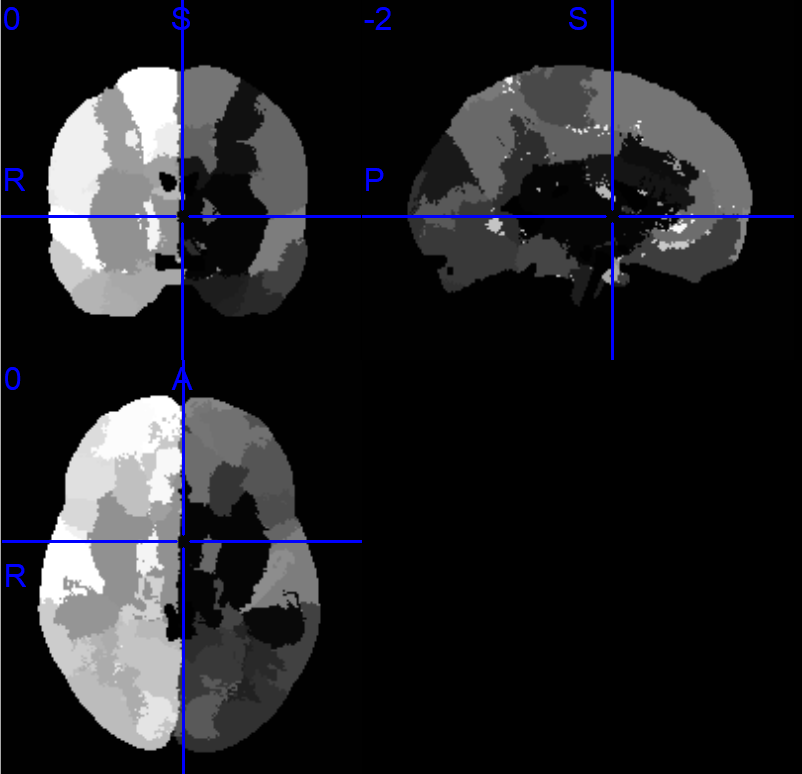

老师您好,我也是想把DK图谱的脑区映射到Yeo 7子网络中,您推荐的这个项目中,给了很多图谱文件,Yeo 7图谱应该是Yeo-7_space-MNI152NLin6_res-1x1x1.nii.gz这个文件,但我不知道常用的DK图谱(包含68个脑区的)是哪一个,烦请老师指教。文件夹中有Desikan_space-MNI152NLin6_res-1x1x1.nii.gz、DesikanKlein_space-MNI152NLin6_res-1x1x1.nii.gz和DKT_space-MNI152NLin6_res-1x1x1.nii.gz三个文件,在MRIcron中打开分别如下:

-

应该是Desikan_space-MNI152NLin6_res-1x1x1.nii.gz,作者在这两个文件里给出了每个脑区的标签: